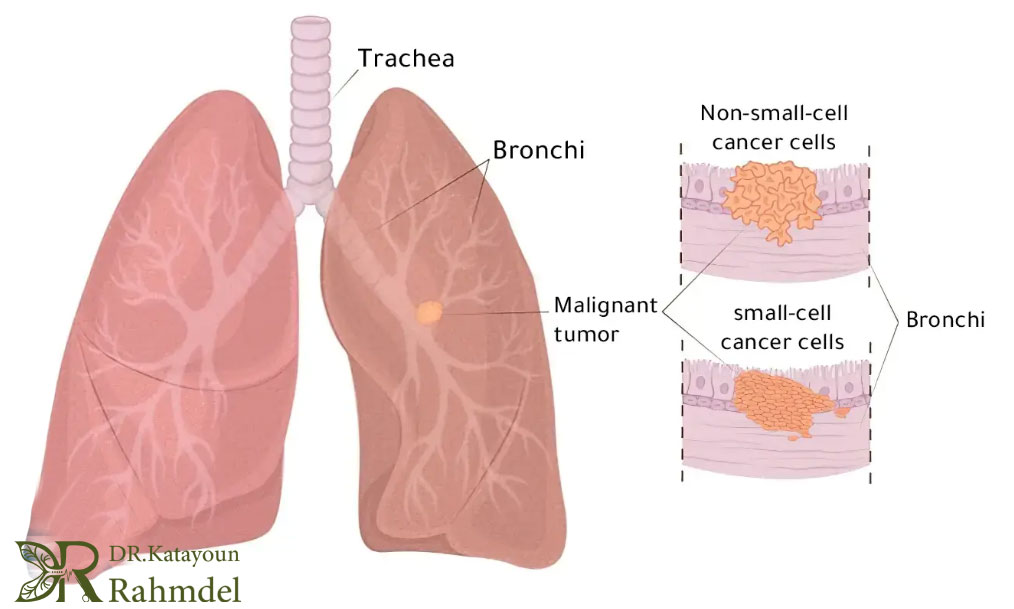

سرطان ریه زمانی رخ میدهد که سلولهای غیرطبیعی در بافت ریه شروع به تکثیر و رشد غیرقابلکنترل کنند. این سلولها میتوانند عملکرد طبیعی ریه را مختل کرده و به تدریج بافت سالم ریه را جایگزین کنند. یکی از ویژگیهای خطرناک سرطان ریه این است که در مراحل اولیه اغلب هیچ علامت واضحی ندارد و همین باعث میشود که بسیاری از بیماران دیرهنگام به پزشک مراجعه کنند. سرطان ریه به دو دسته اصلی تقسیم میشود که هر کدام ویژگیها و روش درمان متفاوتی دارند:

- سرطان ریه سلول غیر کوچک (NSCLC): این نوع حدود ۸۵ درصد موارد سرطان ریه را شامل میشود. رشد آن معمولاً آهستهتر از نوع سلول کوچک است و در مراحل اولیه امکان جراحی موفقیتآمیز بالاتری دارد. درمان NSCLC ممکن است شامل جراحی، شیمیدرمانی، پرتودرمانی یا ترکیبی از این روشها باشد و بسته به مرحله بیماری، انتخاب روش درمانی متفاوت است.

- سرطان ریه سلول کوچک: (SCLC) این نوع حدود ۱۵ درصد موارد را تشکیل میدهد و معمولاً بسیار تهاجمیتر و سریعتر گسترش مییابد . این ویژگی باعث میشود درمان آن دشوارتر باشد و اغلب نیاز به شیمیدرمانی و پرتودرمانی ترکیبی داشته باشد. به دلیل سرعت پیشرفت، تشخیص زودهنگام SCLC اهمیت حیاتی دارد.